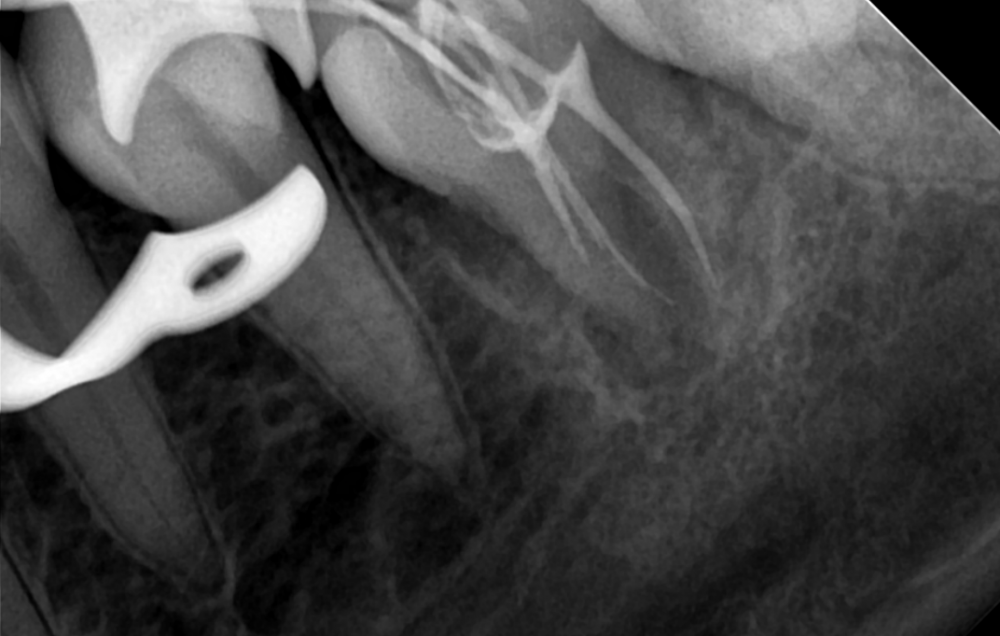

Dr.Deletle Опубликовано 22 июля, 2023 Поделиться Опубликовано 22 июля, 2023 (изменено) Этот кейс интересен тем, что у пересаживаемого 2.8 полностью сформированы корни. Пациент Н., 35лет, зуб 3.6 подлежит удалению по терапевтическим показаниям. Донором был выбран зуб 2.8. Фото №1, 2 - ситуация ДО на фото и срезе КЛКТ Фото №3 - планирование на реконструкции ОПТГ из КЛКТ Фото №4 - шаблон зуба 2.8 Фото №5, 6 - операция, удален 3.6, припасован шаблон, пересажен 2.8 (фиксирован швами и шиной к 3.7) Фото №7 - КТ сразу после пересадки Фото №8, 9 - депульпирование пересаженного 2.8 через 2 недели Фото №10 - снятие шины через 2нед после пересадки Фото № 11, 12, 13 - состояние в полости рта и на срезе КТ через год после пересадки, видно сформированное периодонтальное пространство, здоровая костная ткань, жалоб у пациента нет, полноценно жует как обычным зубом Изменено 22 июля, 2023 пользователем Dr.Deletle 4 3 Ссылка на комментарий

АнтонТЛТ Опубликовано 23 июля, 2023 Поделиться Опубликовано 23 июля, 2023 По этому кт выглядит так, что будто каналы не до конца запломбированы и нет апроксимальных контактов. Ссылка на комментарий